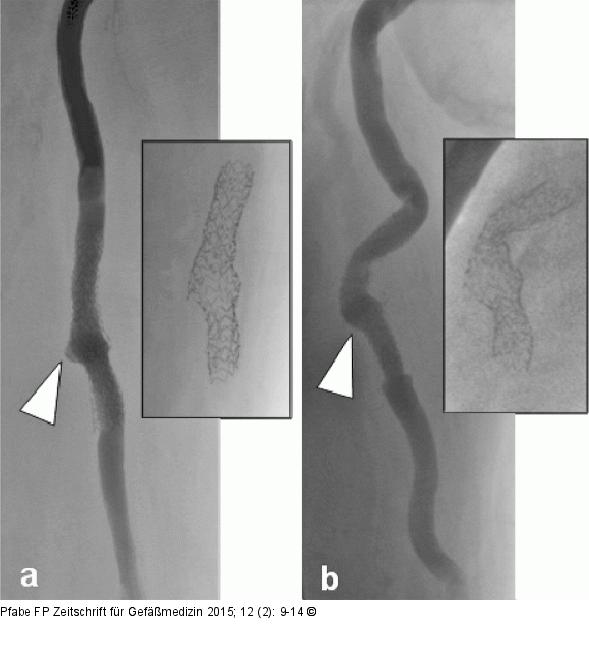

Abbildung 7a-b: Bypass Angiographische Darstellung des Bypass-Verlaufs und der Stentarchitektur. (a): Bei Streckung des Oberschenkels, 12-mm-Pseudoaneurysma nach Stentfraktur Typ III (siehe weißer Pfeil), Destruktion der Stentarchitektur (kleines Bild); (b): angiographische Darstellung der Verlaufsveränderungen des Bypasses bei Oberschenkel-Beugung von 80° im Hüftgelenk, Pseudoaneurysma am Übergang zum bindegewebig fixierten Bypass-Segment (weißer Pfeil), korrespondierende Veränderung der Stentarchitektur (kleines Bild). |